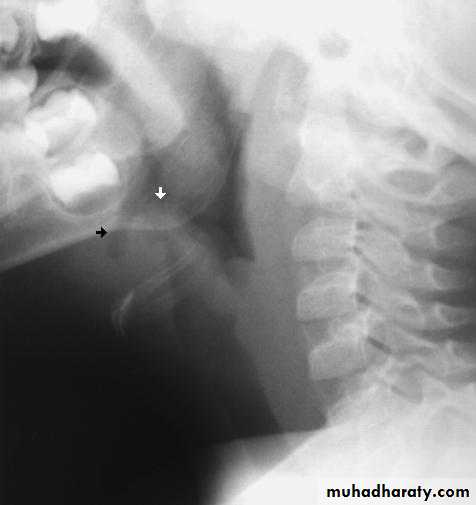

Investigation

Lateral X-ray of the neck may show swollen epiglottis (thumb sign).Treatment